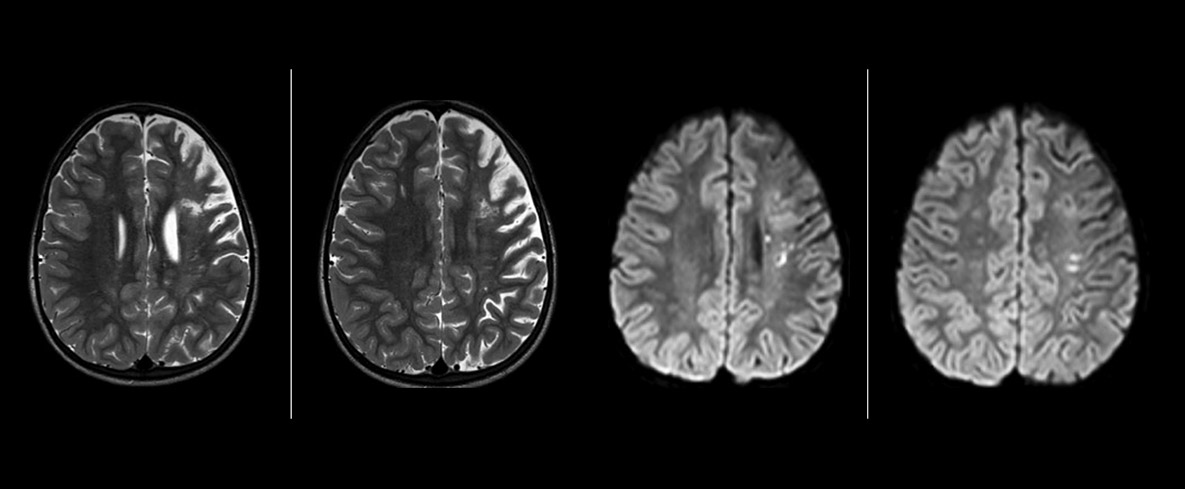

pCASL helps assess brain perfusion without contrast

Pseudo-continuous arterial spin labeling (pCASL) was developed for brain perfusion imaging without contrast agent. “This is very desirable in pediatric patients where the general trend is to limit the administration of contrast,” says Dr. Miller.

Dr. Miller uses pCASL for all patients who present with chronic and acute cerebrovascular abnormalities such as acute stroke, as well as patients who present with signs of acute inflammation in the brain, and occasionally in patients with tumors, to assess the perfusion status of their tumor.

“In combination with diffusion weighted imaging, it can help give a more extended assessment of the degree of perfusion abnormality in a patient who is suffering acute ischemia. We have a number of patients who have chronic arterial insufficiency due to prior arterial abnormalities or acquired arterial abnormalities such as sickle cell disease or neurofibromatosis. Sometimes the child’s first manifestation of disease progression is a reduction in brain perfusion before stroke symptoms manifest clinically or in diffusion weighted imaging. We use pCASL to help delineate the perfusion abnormality.”

Growing confidence in specific applications

“We built up confidence in pCASL by comparing it to contrast-based perfusion imaging. Once we had confidence that it was representing what the contrast perfusions were representing, we increased our diagnostic confidence by serial imaging in either the acute stage or the long term stages in a number of patients with arterial abnormalities.